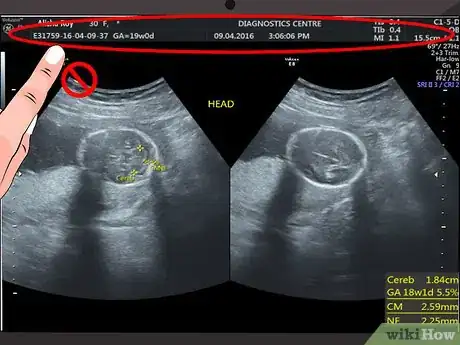

1Disregard the text and numbers at the top of your scan. Most hospitals and ultrasound centers use this space to include details like your name, hospital reference number, or ultrasound machine settings. Since this information does not have anything to do with what you see on the ultrasound image, you can ignore this information.[1]

2Start from the top of the image. The top of the screen or printed image is where the ultrasound probe was placed. In other words, the image you see shows what the organ or tissues look like from the side rather than from the top.[2]

- For example, if you are having an ultrasound of your uterus, then what you see at the top of the screen or printed ultrasound would be the outline of the tissues above your uterus. As you look further down the screen, you will see deeper tissues, such as the lining of your uterus, the inside of your uterus, and the back of your uterus.